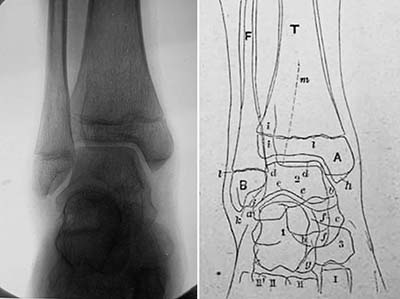

《1918-20-正常四肢骨のレントゲン写真図譜》

レントゲン写真図譜 (第一輯~第四輯)

藤浪剛一(朝香屋書店,1918-20)

図10. 10歳男児の右手.手根骨が3個骨化している.

図11. 16歳女児の左足関節.

藤浪は序文で,欧米のようなレントゲン図譜が本邦にはないことを憂い,かねてよりこれを企画していたものの,出版者が写真を鮮明に印刷する技術を持たず実現できなかったが,本書の出版社である朝香屋の主人がこれを引き受けてくれてようやく発刊できたと述べている.レントゲン図譜と銘打っているが,その内容は専ら四肢骨の正常像で,小児の骨化中心の出現に主眼が置かれている.藤浪は,ウィーン留学中に手根骨の骨化順序に関する論文を2篇著しており,その延長上にあるものと思われる.

第一輯から第四輯まで四分冊で,それぞれ手関節,肘・肩関節,足関節,膝関節の正常像を扱い,全58葉のレントゲン写真とそのスケッチが,小児から成人まで年齢順に供覧されている(図10,図11).写真の画質はかなり良好で,現在でも充分通用する解像度を備えている.

藤浪の著書で,放射線診断学領域を扱ったものは,本書の他には「内臓レントゲン診断学」および「れんとげん学」があるが,胸腹部の内臓疾患については詳細に書かれているものの,奇妙なことにそのいずれも骨格系の診断については全く触れていない.欧米では既にこの時期,骨折や骨端症の画像所見が数多く報告され,教科書も書かれていることを考えると疑問に思うところであるが,藤浪は特にこの点について言及していない.その意味で本書は,正常像のみであるが骨格系のレントゲン像を記載した唯一の著書である.